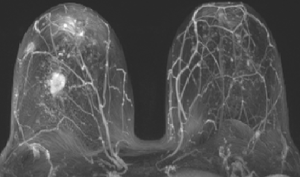

МР-диагностика новообразований молочных желез

- Диагностика и стадирование рака молочной железы